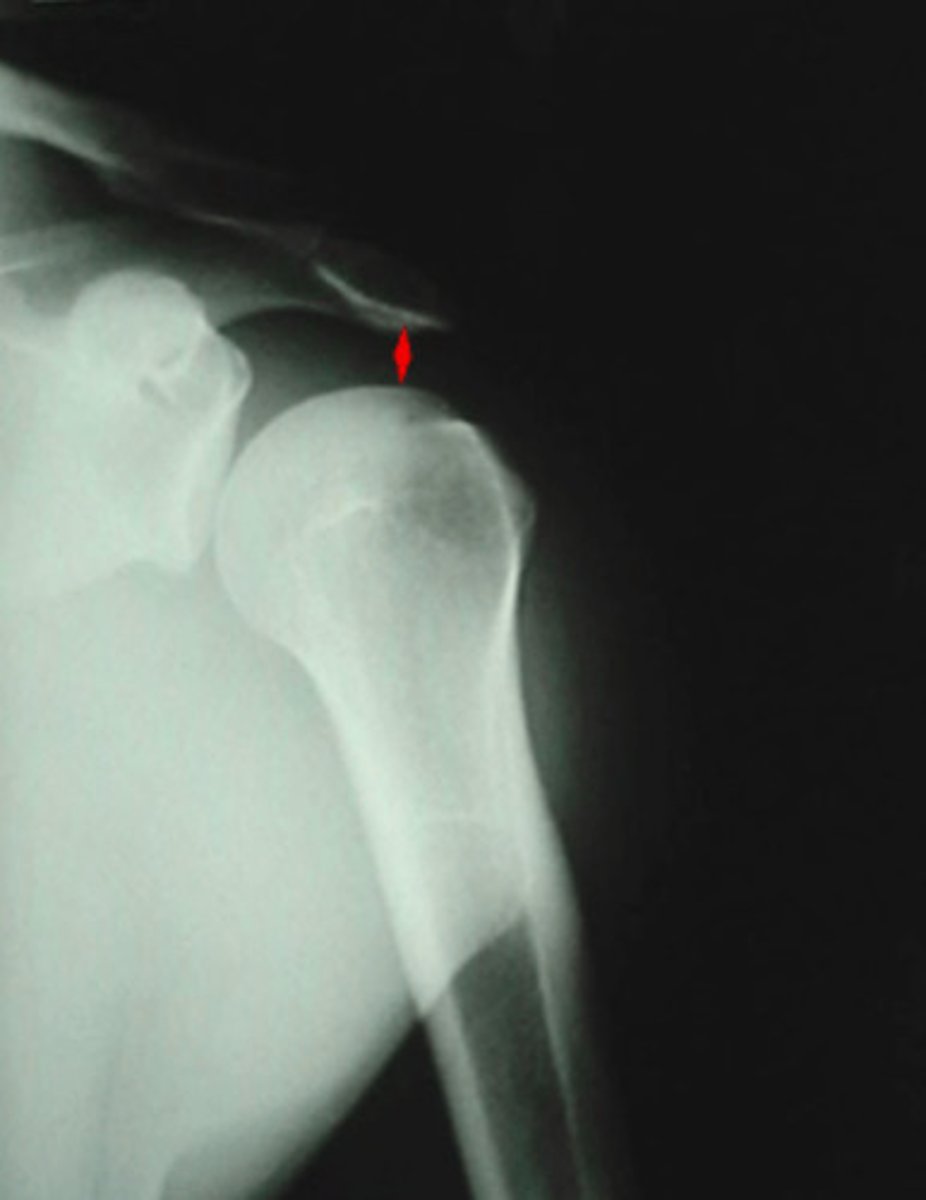

Acromiohumeral joint space

What space is being indicated in this image?

7-11 mm

What is the normal measurement for the Acromiohumeral joint space?

Acromion process

What is being pointed out by the arrow in the image?